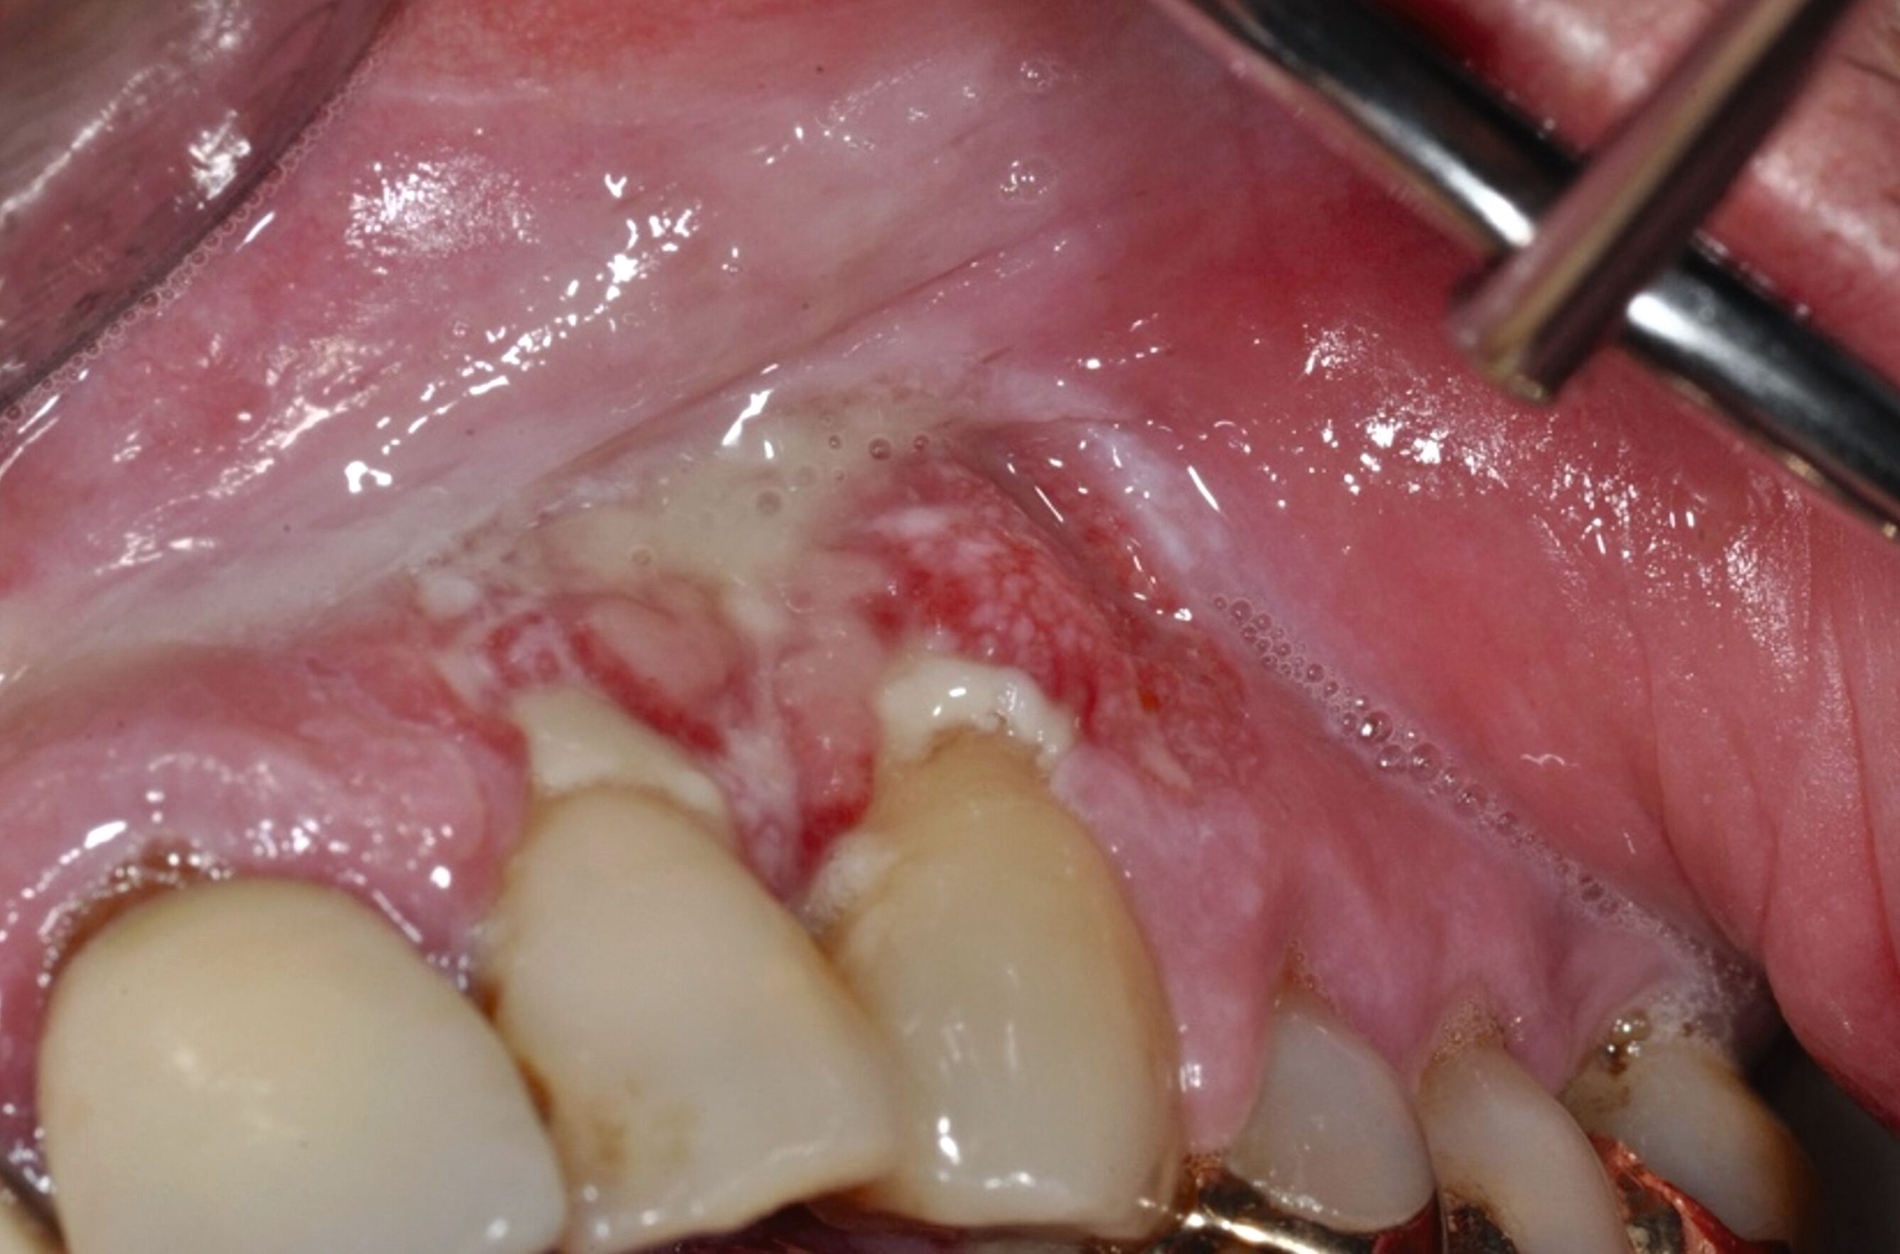

Ein 60-jähriger Patient berichtet über brennende Schmerzen im Mundraum und zeigt weiße und erythematöse Läsionen an der Zunge und im vestibulären Oberkiefer (Abbildungen 8 und 9). Eine Biopsie bestätigt die Diagnose eines erosiven Lichen planus. Eine Kombination aus topischen und systemischen Kortikosteroiden wurde verordnet und der Patient bei Besserung der Symptome in die enge Nachsorge (alle zwei bis vier Monate) entlassen.